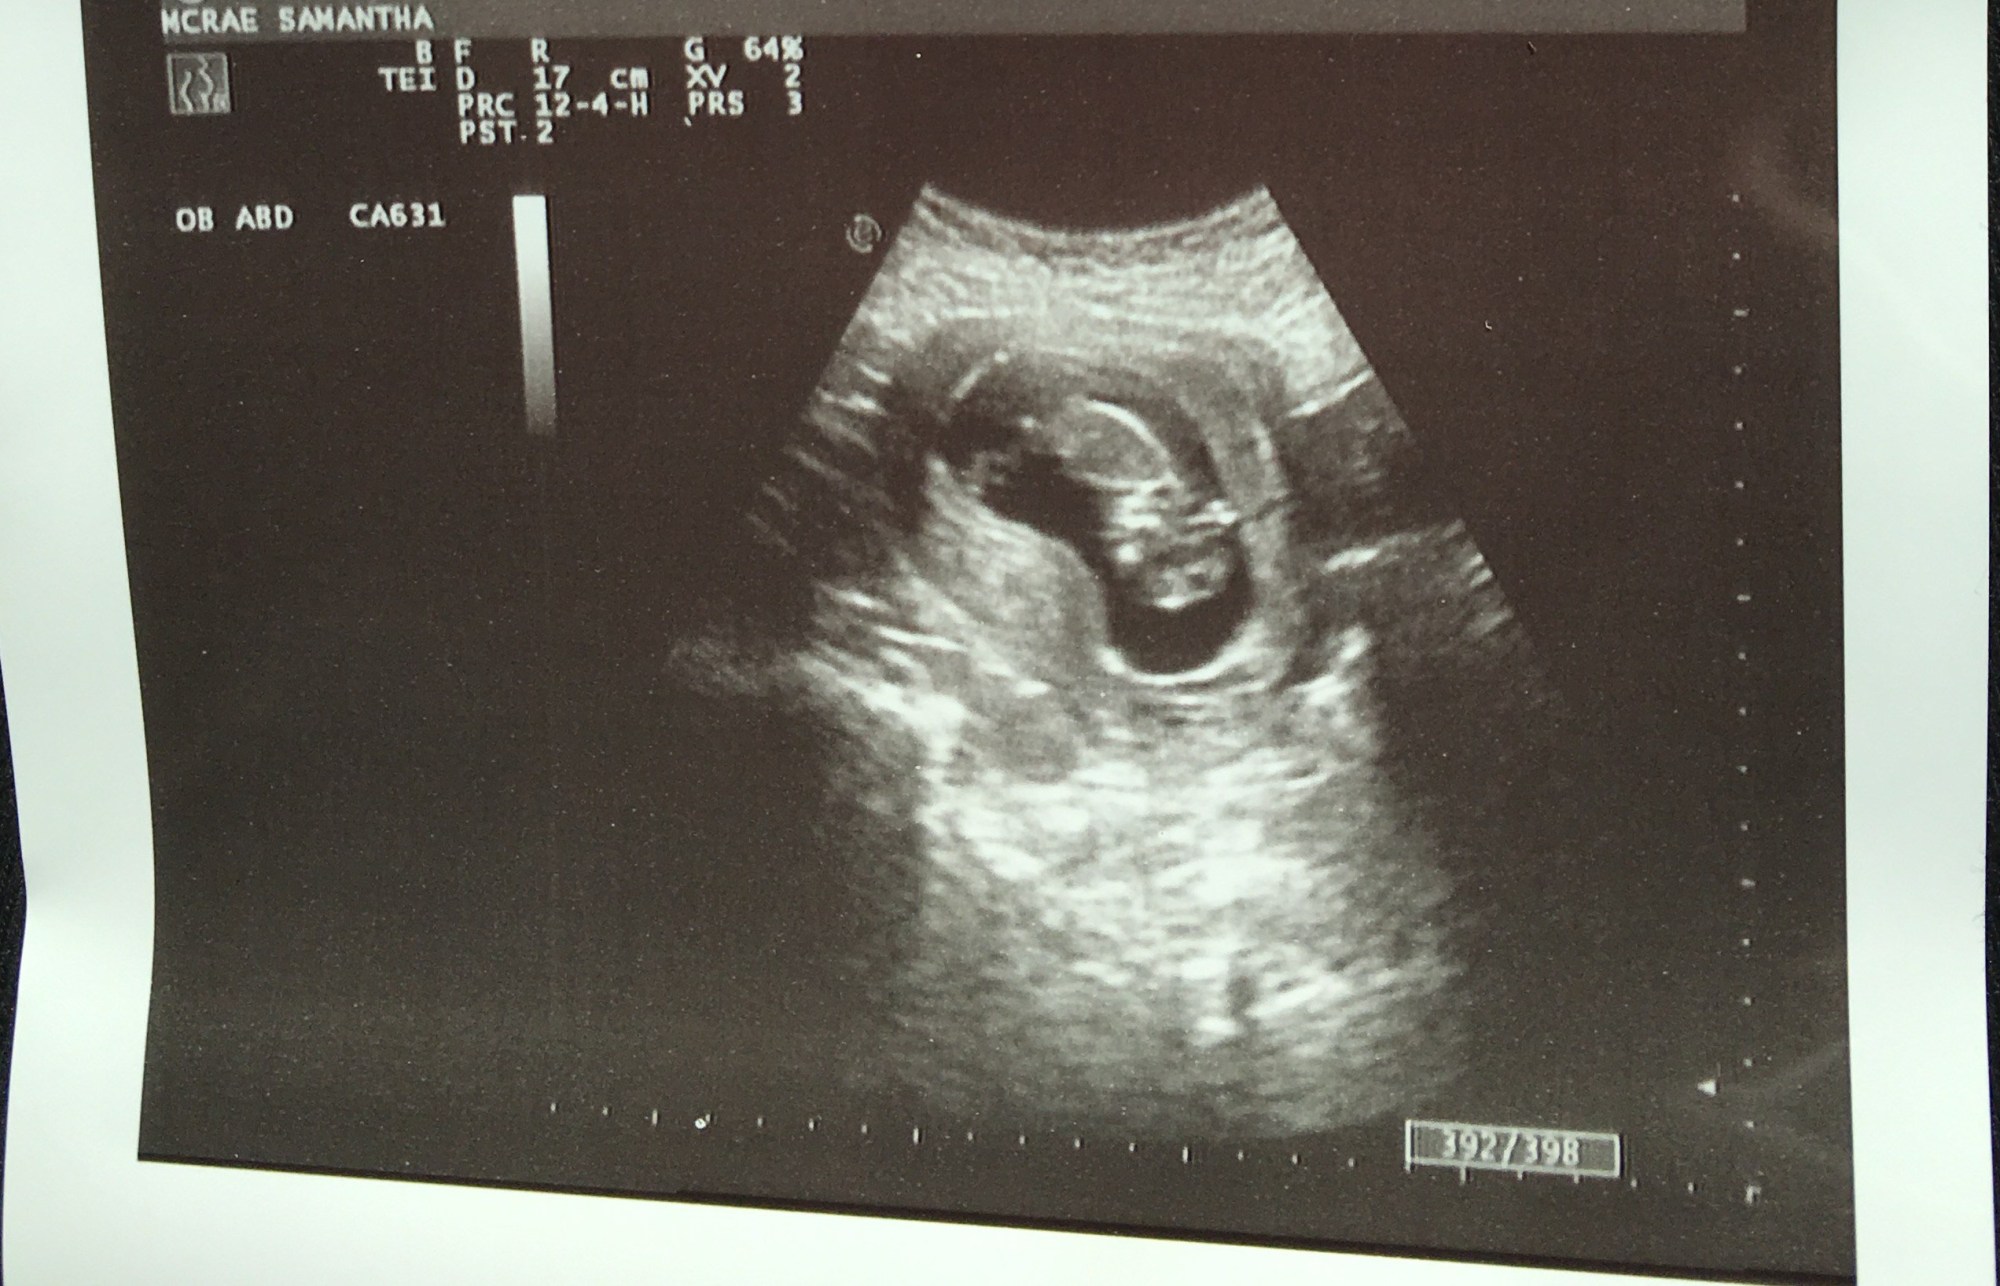

Finally, Samantha and I have some exciting news to get out in the open…

That’s right! We’re having a baby!!! 😀

With a due date of August 30th, Samantha is 12 weeks along, and we couldn’t be more excited about this wonderful gift!